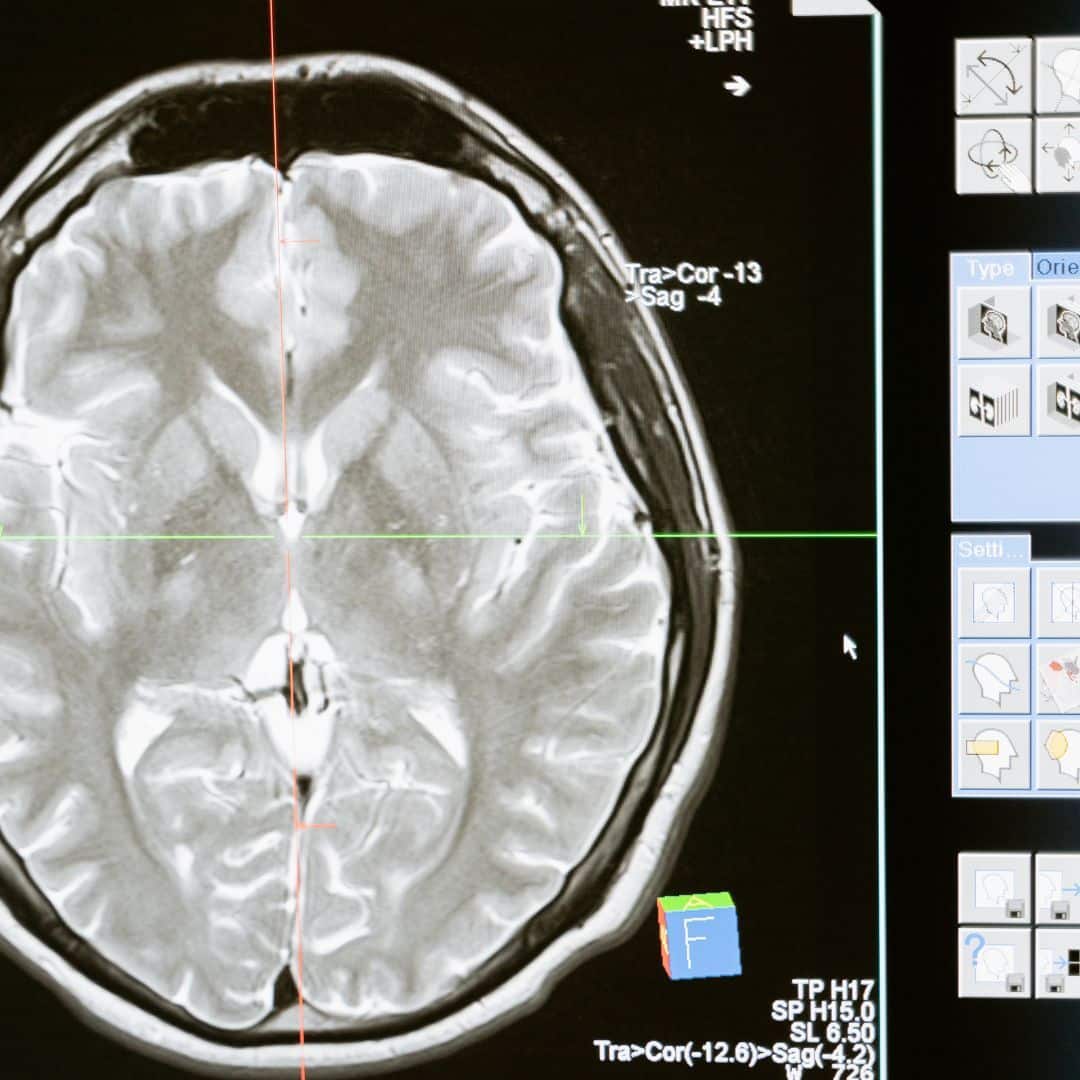

Neuroscience encompasses various disciplines, including biology, psychology, and computer science. At its core, it studies how neurons communicate, the structure of the brain, and how these elements give rise to behavior and cognitive functions. By examining the nervous system at molecular, cellular, and systemic levels, neuroscientists aim to unravel the mysteries behind learning, memory, emotion, and decision-making.

The field is vast and includes several branches, such as cognitive neuroscience, neurobiology, and clinical neuroscience. Cognitive neuroscience focuses on understanding the brain’s role in mental processes, while neurobiology examines the biological aspects of nervous systems, including cellular mechanisms. Clinical neuroscience applies this knowledge to address neurological disorders, aiming to improve diagnosis and develop effective treatments.

Research in neuroscience is crucial for addressing various health challenges, including mental illness, neurodegenerative diseases, and brain injuries. By advancing our understanding of the brain, researchers can develop targeted therapies that improve patient outcomes. Organizations like the ANF play a vital role in funding and supporting innovative research efforts that pave the way for new treatments.